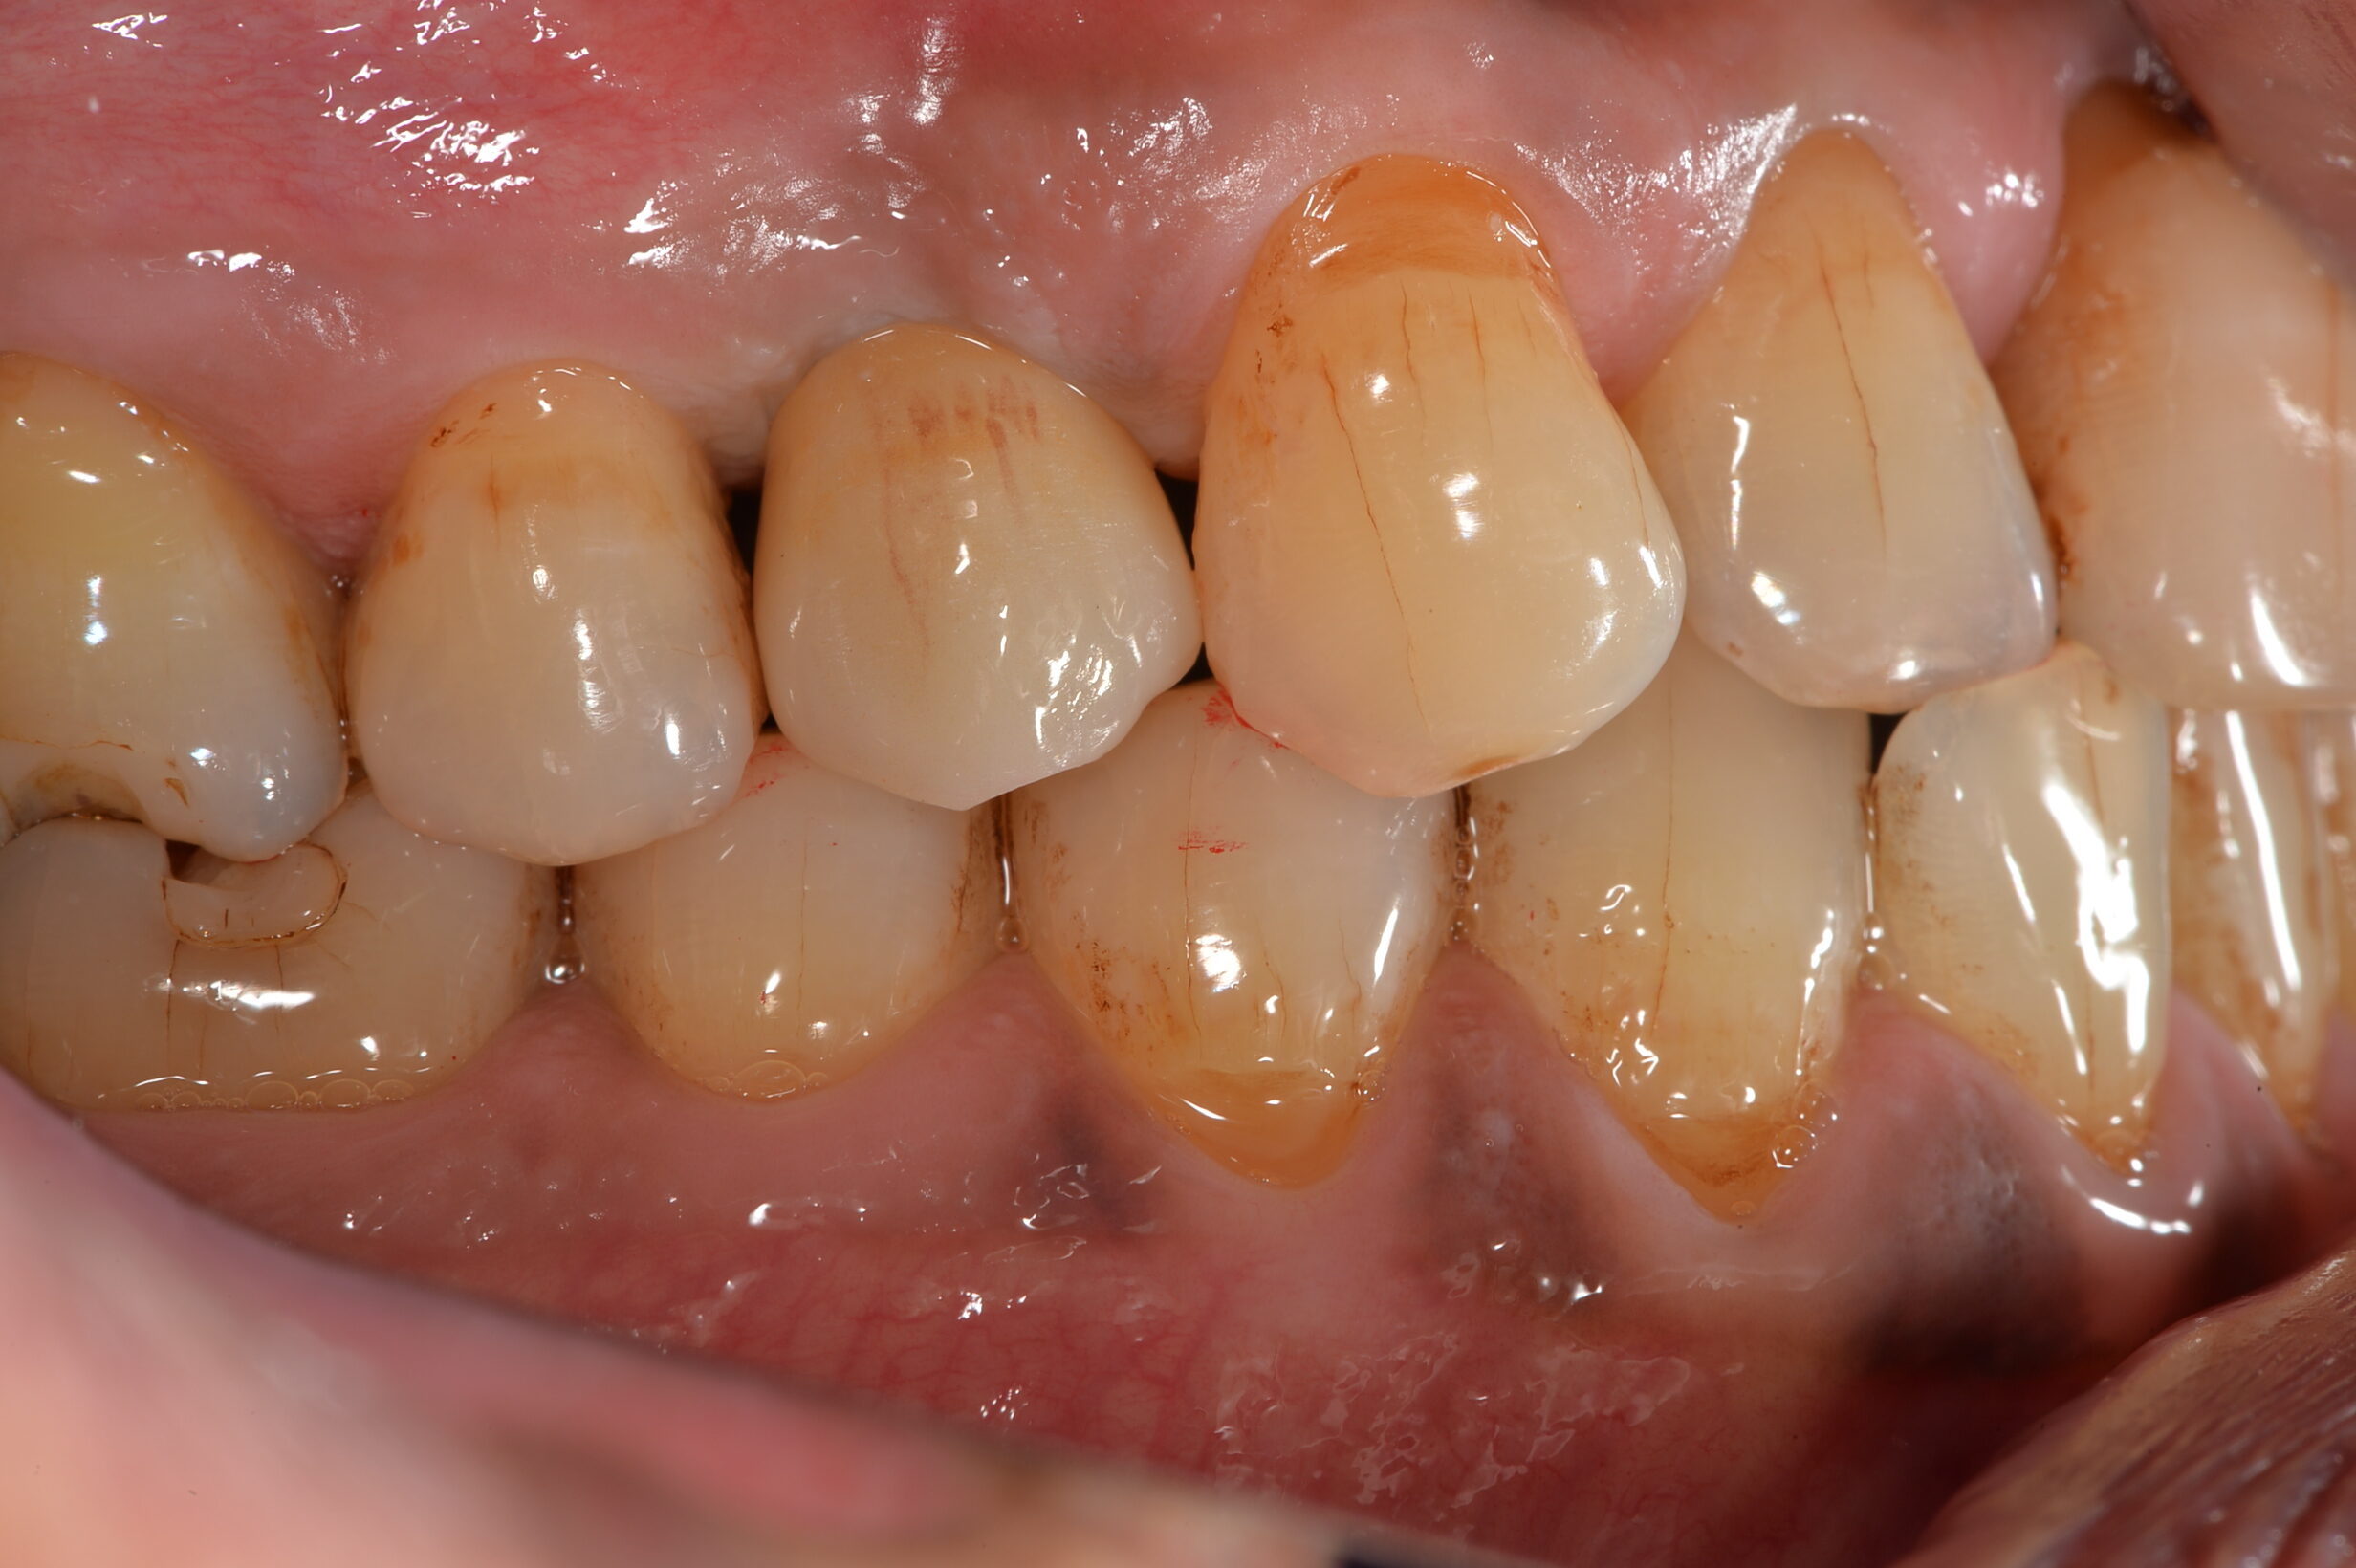

Before

| 主訴 | 膿んでいる。噛むと違和感がある。 |

| 診断名 | 慢性根尖性歯周炎 |

| 年齢・性別 | 50代・男性 |

| 治療期間・回数 | 6ヶ月~1年・5回 |

| 治療方法 | 待時インプラント |

| 費用 | 400,000円~450,000円【税込み】(インプラント1本あたり) |

| デメリット・注意点 | ・保険適用外の自由診療範囲となるため治療費が保険診療より高く感じる場合があります ・外科手術が必要になるため、患者さんに体力的な負担がかかります ・段階的に治療を進めていくため、治療期間が長くなります ・術後に痛み・腫れ・出血・合併症を伴う可能性があります ・術後も定期的なメンテナンスをしないと、機能が落ちやすくなります |